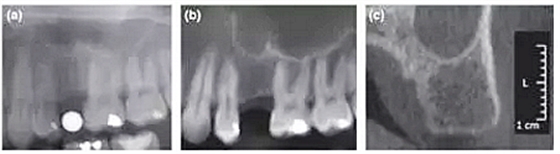

本研究共納入71名患者,所有擬種植位點行數(shù)字化全景(D-PAN)及錐束CT(CBCT)檢查。攝全景片時,將一直徑5 mm的金屬球置于缺牙區(qū)。重組CBCT數(shù)據(jù)組分別構(gòu)建10 mm層厚的CBCT全景圖像(CBCT-pan)及1 mm層厚的斷面影像(CBCT-cross)。三名測量者在顯示器上應(yīng)用專業(yè)軟件測量圖像,在擬種植位點放置4個參考點以模擬種植體外形。分析比較根據(jù)3種影像選擇的種植體長度和直徑的差異。并且針對每種種植系統(tǒng),比較根據(jù)CBCT-cross與其他2種方式(D-PAN和CBCT-pan)選擇的種植體尺寸。

結(jié)果顯示,根據(jù)CBCT-cross選擇的種植體(3個觀察者取平均值)比D-PAN和CBCTpan選擇的種植體直徑更小。在前磨牙區(qū)域,D-PAN和CBCT-pan選擇的種植體直徑也有顯著差異。相比D-PAN,CBCT-cross選擇的種植體顯著更短。在前磨牙位點,3種測量方式選擇的種植體長度無顯著差異。CBCT-cross選擇的種植體尺寸級別相比D-PAN和CBCT-pan無顯著差異。

總結(jié)來說,本研究的結(jié)果表明利用CBCT重建全景片與CBCT斷層影像選擇的種植體尺寸存在差異。在大多數(shù)病例中,相比全景片或CBCT重建全景片,根據(jù)CBCT斷層影像測量并選擇的種植體直徑和長度均更小。